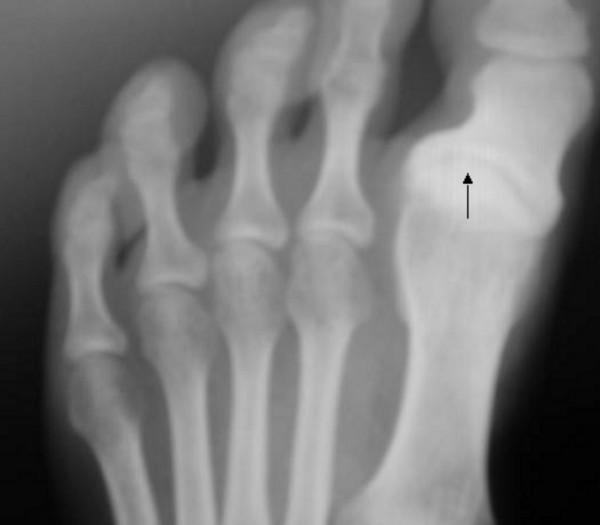

The phenotype of Stickler syndrome can be diverse and therefore misleading. The expectation that the full clinical criteria of any given genetic disorder such as Stickler syndrome will always be present can easily lead to an underestimation of these serious inheritable disorders. We report here two family subjects, a male proband and his aunt (paternal sister), both presented with the major features of Stickler syndrome. Tall stature with marfanoid habitus, astigmatism/congenital vitreous abnormality and submucus cleft palate/cleft uvula, and enlarged painful joints with early onset osteoarthritis. Osteochondritis dissecans (OCD) and Osgood Schlatter syndrome (OSS) were the predominating joint abnormalities.

We observed that the nature of the articular and physeal abnormalities was consistent with a localised manifestation of a more generalised epiphyseal dysplasia affecting the weight-bearing joints. In these two patients, OCD and OSS appeared to be the predominant pathologic musculoskeletal consequences of an underlying Stickler's syndrome. It is empirical to consider generalised epiphyseal dysplasia as a major underlying causation that might drastically affect the weight-bearing joints.

成骨不全症的表型可能多种多样,因此具有误导性。期望任何特定遗传疾病(如成骨不全症)的全部临床标准总是存在,这很容易导致对这些严重遗传性疾病的低估。我们在这里报告了两个家族患者,一个男性先证者和他的姑姑(父亲的妹妹),都表现出成骨不全症的主要特征。身材高大,马凡体型,散光/先天性玻璃体异常,黏膜下腭裂/悬雍垂裂,以及大关节疼痛,早期出现骨关节炎。骺软骨分离(OCD)和 Osgood-Schlatter 综合征(OSS)是主要的关节异常。

我们观察到关节和骺板的异常性质与影响承重关节的更广泛的骺发育不良的局部表现一致。在这两个患者中,OCD 和 OSS 似乎是潜在成骨不全症的主要骨骼肌肉病理后果。考虑到普遍的骺发育不良是一个主要的潜在病因,这可能会严重影响承重关节,这是一种经验性的看法。